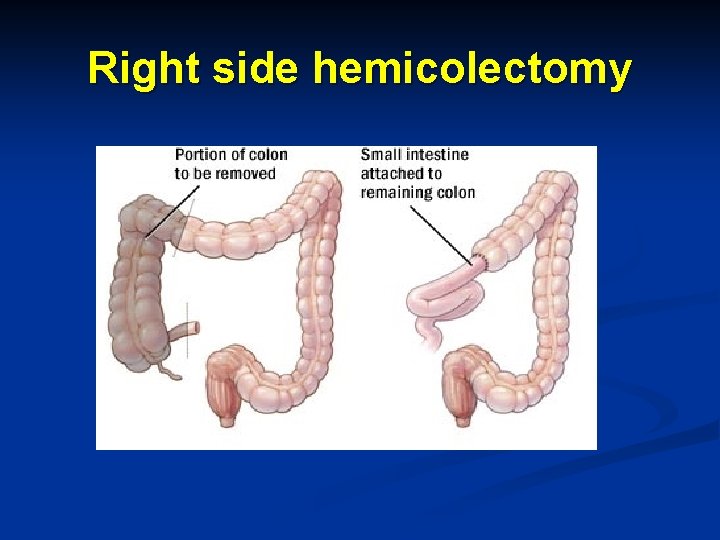

Right side hemicolectomy